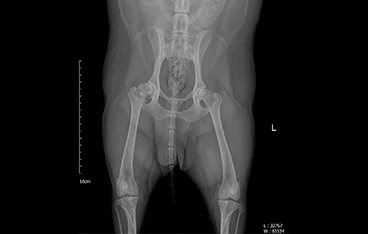

• 골반골절

• 골반골절 수술 전

골반골절 수술 후